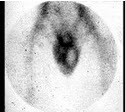

42、单项选择题

患者38岁,主诉左侧阴囊疼痛2天,查体见左侧阴囊稍红肿如图。超声检查基本正常。最可能的诊断是()

A.左侧睾丸蒂扭转

B.左侧附睾睾丸炎

C.未见明显异常

D.右侧睾丸蒂扭转

E.右侧睾丸附睾炎